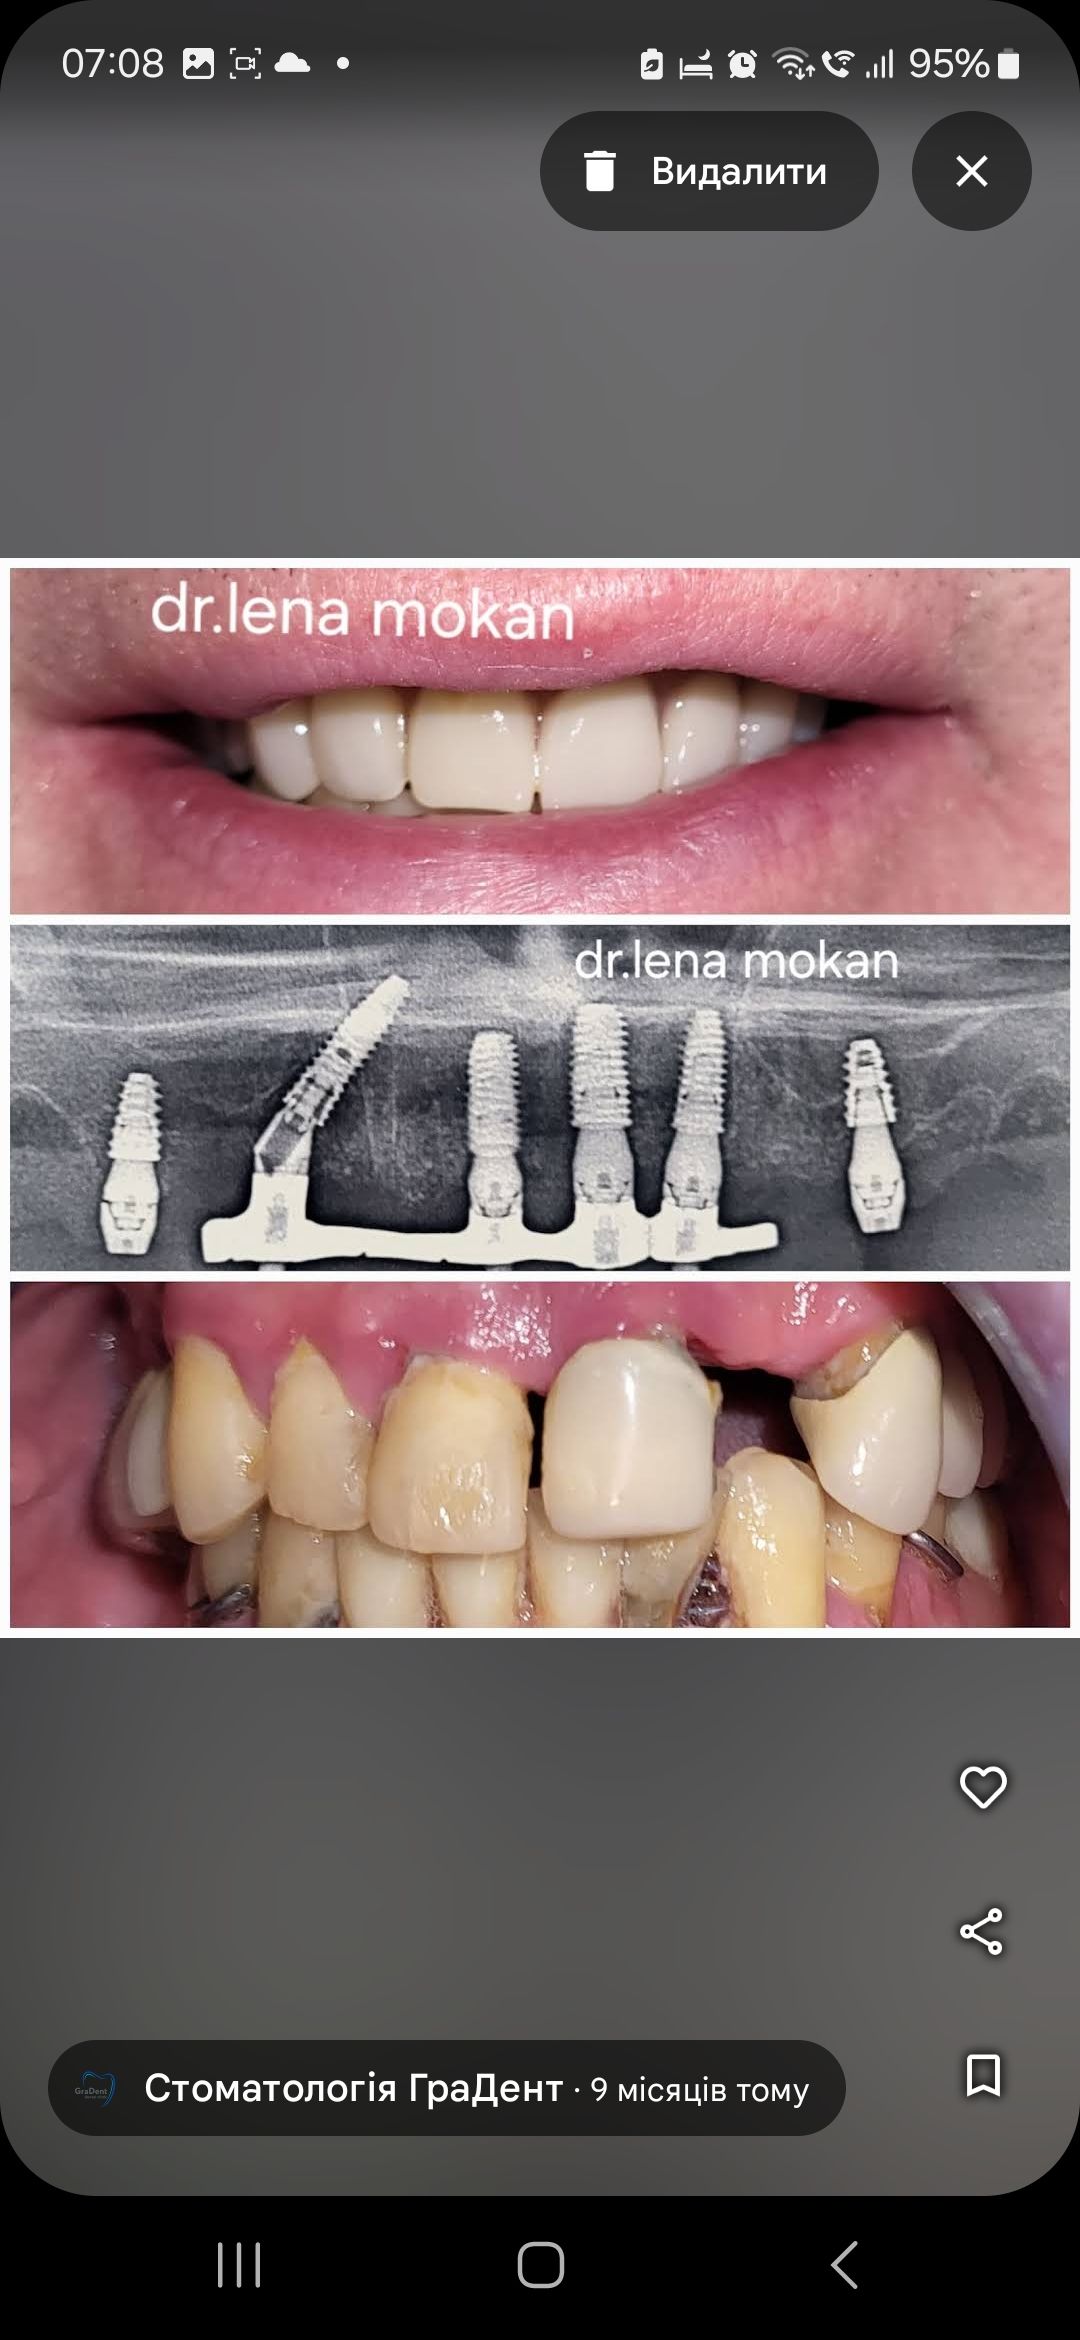

У стоматології МоканДент ми пропонуємо послуги з імплантації зубів, які допомагають відновити не лише вашу усмішку, але й функціональність зубів. Ми працюємо за світовими стандартами імплантації та встановлюємо корейські імпланти фірми OSSTEM.

Зубні імплантати – це сучасне та ефективне рішення для відновлення втрачених зубів, яке надає стабільний функціональний та естетичний результат. Вони інтегруються з природними тканинами щелепи, забезпечуючи надійне кріплення та повернення комфорту у щоденному житті.

Коронки та мости – це ефективні стоматологічні рішення, які використовуються для відновлення пошкоджених чи втрачених зубів. Коронки надають індивідуальний захист та відтворюють природний вигляд, а мости заміняють відсутні зуби, відновлюючи функціональність та естетику усмішки.